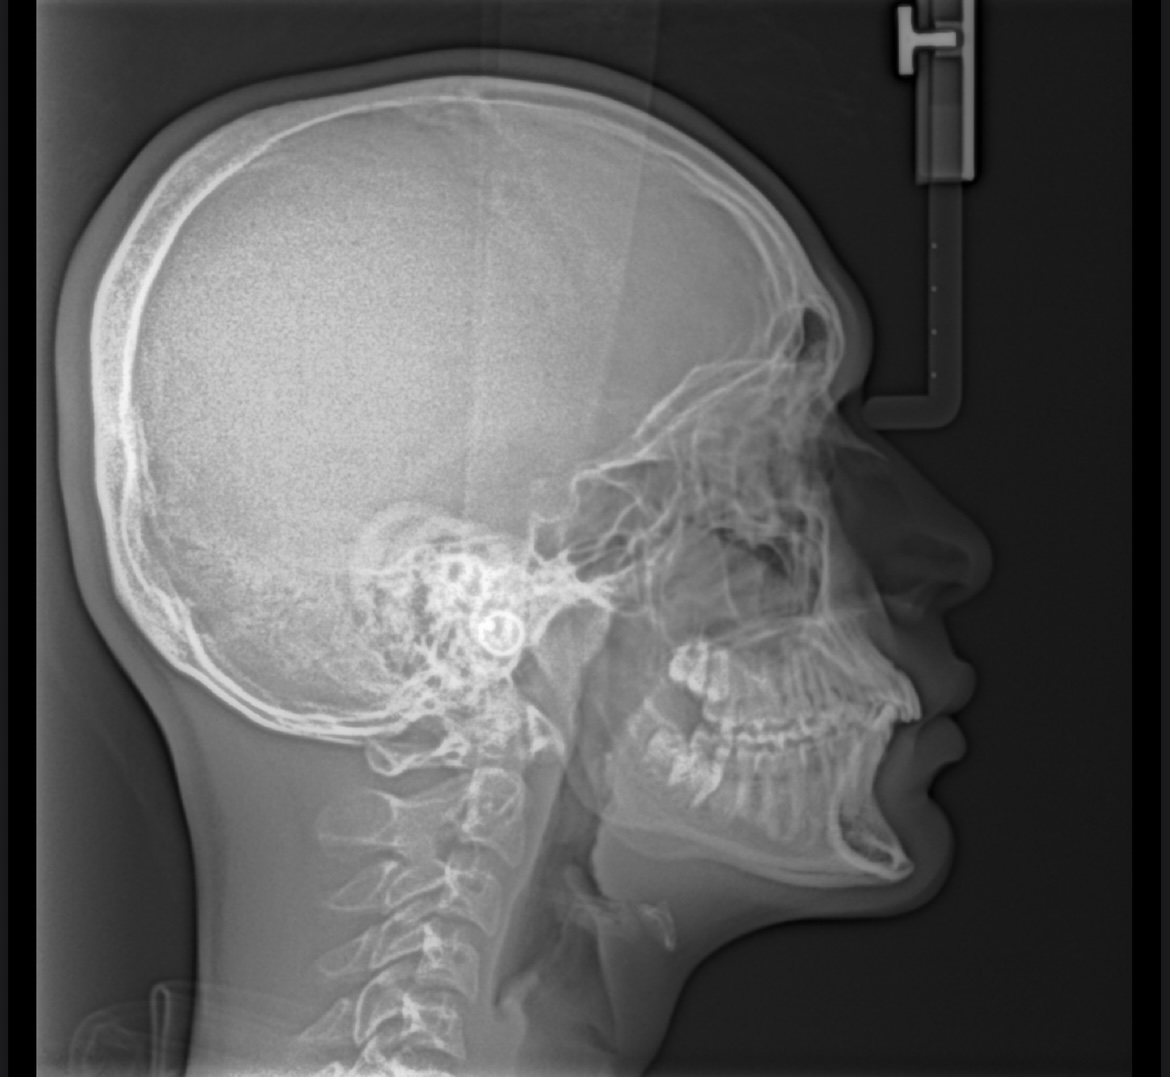

IMG 6580

How recessed am I? I’m 18 and I feel so shit since I got the X-ray. Also I’d be glad if HighIQcels can measure the SNA and SNB angles

View attachment 4522364How recessed am I? I’m 18 and I feel so shit since I got the X-ray. Also I’d be glad if HighIQcels can measure the SNA and SNB angles

Not ridiculously recessed but you are recessed

I would measure the SNA & SNB but I'm doing stuff with friends rn, you can measure angles urself using some online websites/software like ImageJ

SNA / SNB Doesn't matter for aesthetics. But yeah you are recessed

Ik I’m recessed cuz my side profile look like this similar to vito basso, but by how much? Whereas my ortho said I’m not idk why